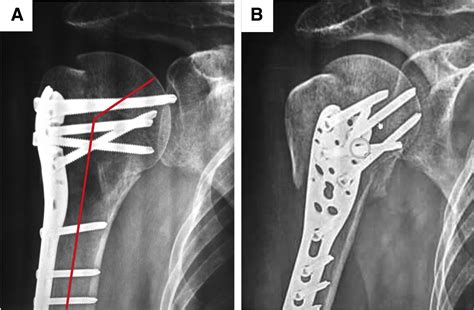

The term Open Reduction And Internal Fixation describes two distinct parts of a surgical process. "Open reduction" refers to the surgeon making an incision to access the bone directly and reposition the fractured segments so they align properly. "Internal fixation" refers to the method of holding the bone in place using specialized medical hardware, such as metal plates, screws, pins, or rods.

- Fixation: Once aligned, the surgeon attaches hardware to stabilize the fragments. This might involve placing a titanium or stainless steel plate across the break and securing it with small screws.

⚠️ Note: The type of hardware used—whether it is a plate, screw, or intramedullary nail—depends heavily on the specific bone affected and the nature of the fracture pattern.